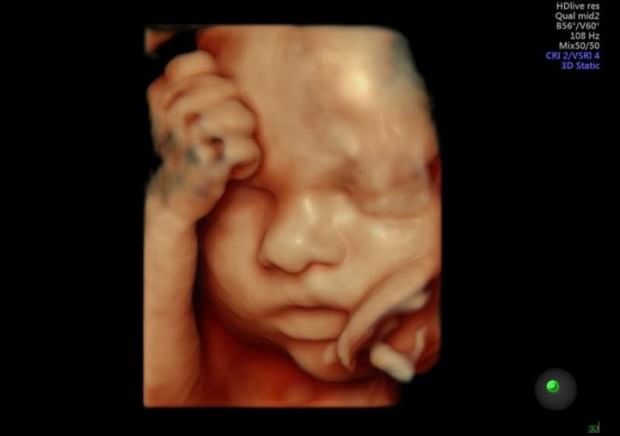

Ultrason cihazlarının çalışma şekli ise, insan kulağıyla duyulamayan yüksek frekanslı ses, bir prob (transducer) aracılığıyla dokuya yollanır. Daha sonra farklı yoğunluklardaki dokularda titreşen ses dalgaları bir monitörde (ekran) görüntülenir. İlerleyen teknoloji sayesinde artık ekrana yansıyan bu görüntüler daha net kalitede ve 4 boyutlu olarak görülmektedir. 4 boyutlu ultrason cihazı diğer boyutlara nazaran ekrana görüntüyü daha net getirerek, dokulardaki detayların ayrıştılması bile yapılabilir.

4 boyutlu ultrason ile bebeğin gerçeğe yakın görüntüsü görülebilir. Bu yöntem ile bebeğin sağlıklı olup olmadığı, cinsiyeti ve kime benzediği bile rahatlıkla fark edilebilir. Klasik 2 boyutlu ultrason düz bir açıyla ayrıntısız görüntü verirken, 4 boyutlu ultrasonda her ayrıntı vardır.

- 4 boyutlu ultrasonun en büyük avantajı, bebeğin, yarık dudak, yarık damak, eksik parmaklar, omurilikten kaynaklanan rahatsızlıklar gibi fiziksel sorunların erken tanısıdır. Çünkü 2 boyutlu ultrasonda el ve ayaklardaki rahatsızlıklar net olarak görülemeyebilmektedir.

- Ense kalınlığının, 4 boyutlu ultrasonla ölçülerek bebekte, down sendromu olup olmadığı rahatlıkla görülebilmektedir.

- Bebeklerin, bir film gibi canlı görüntüleri sayesinde, gelişimleri çok daha detaylı incelenmektedir.

- Bebeklerin cinsiyetleri ve renkli görüntüleri net bir şekilde elde edilir.

- Ebeveynler bebeğin kime ve neye benzediğini çok merak ettikleri için 4 boyutlu ultrason sayesinde bebeğin ağzını, burnunu, yüzü ve çenesini, el ve ayaklarını net bir şekilde görebilmektedirler.